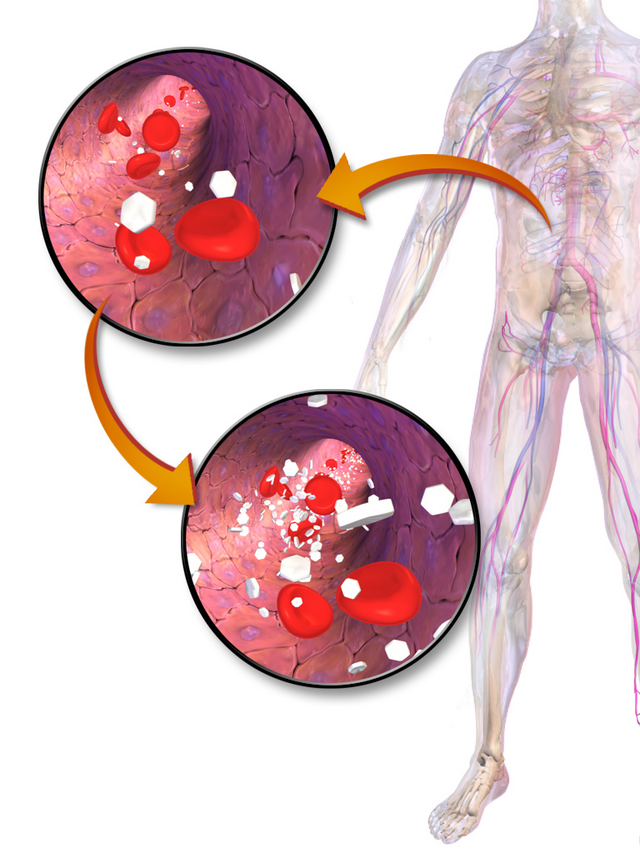

‘저혈당’(hypoglycemia)은 말 그대로 혈중 포도당 농도가 정상 범위 이하로 떨어진 상태를 말합니다.

혈당이 떨어지면, 뇌와 신경계는 에너지원 공급에 차질을 빚고 즉각적인 이상 신호를 보내기 시작합니다.

- 뇌는 포도당을 유일한 에너지원으로 사용합니다.

- 따라서 혈당이 떨어지면 뇌 기능이 가장 먼저 손상됩니다.

- 저혈당이 지속되면 의식 소실, 발작, 혼수상태로까지 이어질 수 있으며

✅ ② 식은땀

혈당이 60mg/dL 이하로 떨어지면 자율신경계가 흥분하여 갑작스럽게 식은땀이 나기 시작합니다.

혈당이 떨어지면 교감신경이 활성화되어 말초 신경 자극이 증가합니다.

이로 인해 손이나 입술, 턱이 떨리고, 체온은 정상인데도 한기가 느껴질 수 있습니다.